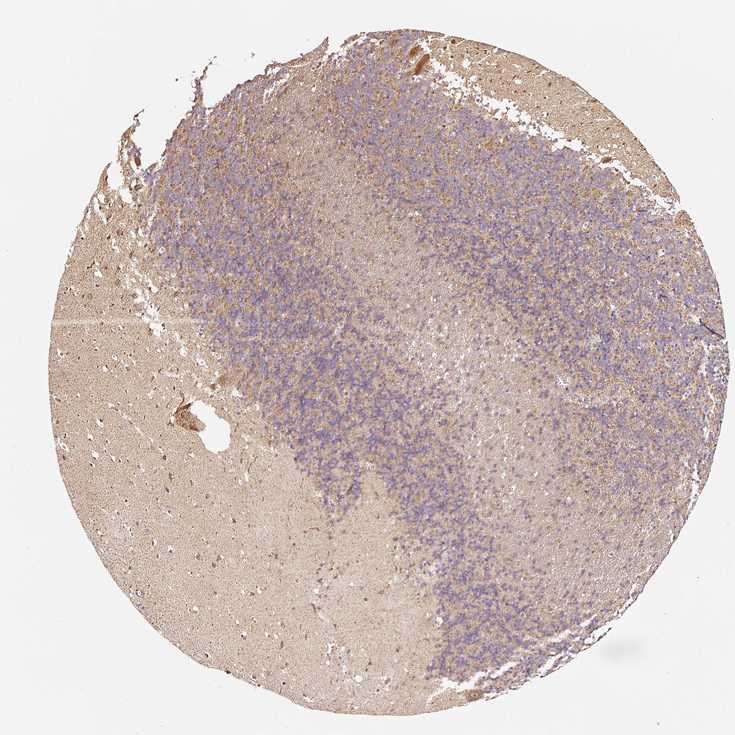

Antibody staining in the annotated cell types in the current human tissue is reported as not detected, low, medium, or high. This score is based on the staining intensity and fraction of stained cells.